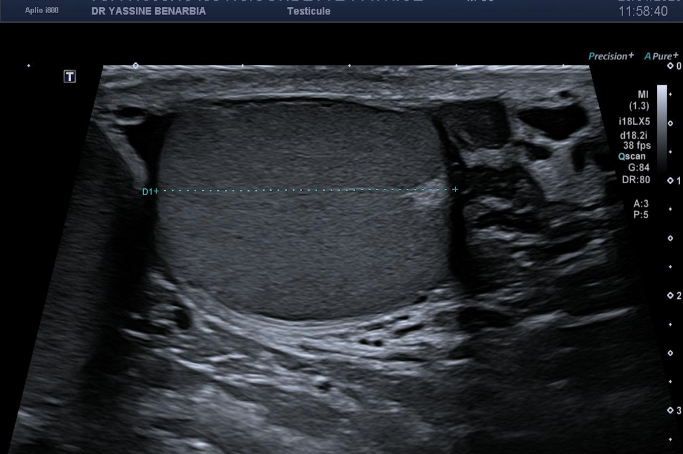

L'échographie retrouve des testicules de morphologie, taille et vascularisation strictement normales bilatéralement. Les épididymes sont également normaux, sans signe d'inflammation. Le Doppler couleur montre une vascularisation testiculaire symétrique et physiologique.

L'exploration de la région inguinale est donc réalisée révélant une hernie inguinale gauche indirecte avec un sac herniaire contenant des anses grêliques lors des manœuvres de Valsalva. Le collet herniaire mesure 20 mm lors de l'hyperpression abdominale. La hernie est parfaitement réductible et ne présente aucun signe de complication (péristaltisme conservé, paroi digestive fine, vascularisation normale au Doppler).